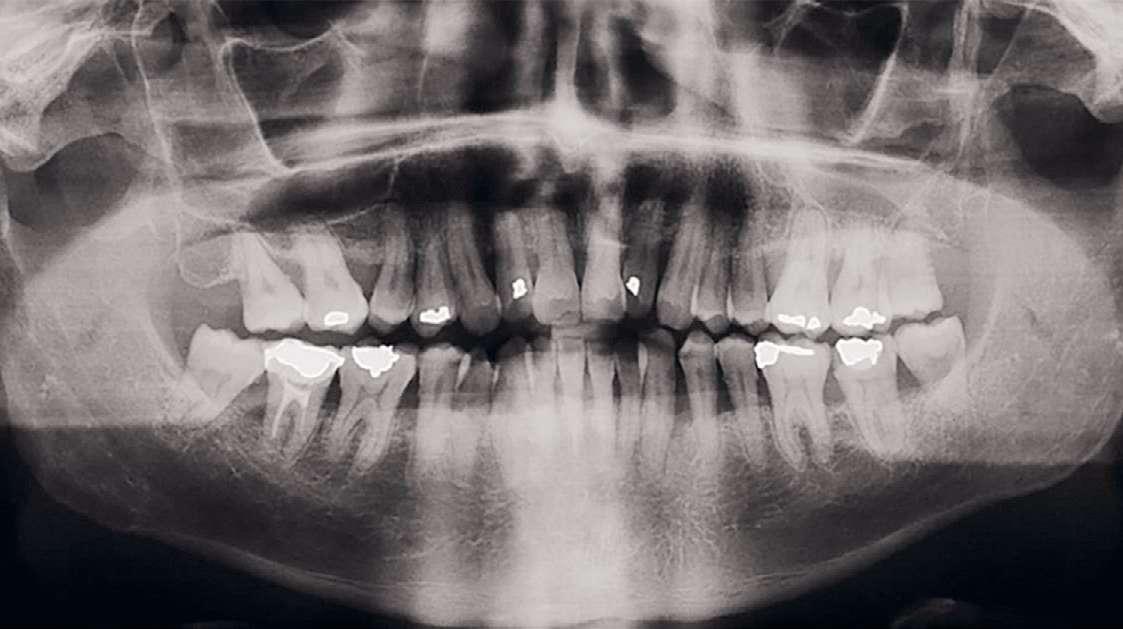

El examen radiográfico (Figuras 3 y 4) reveló, además de una pérdida ósea horizontal generalizada, la presencia de defectos intraóseos a nivel de 1.2 y 3.3. Según el algoritmo de Tonetti y Sanz (2019), al no presentar registros previos se determinó el grado por medio de la evidencia indirecta, para lo cual se tomó el diente con mayor afectación periodontal, tratándose del 3.4, y valorando la pérdida ósea en relación con la edad, siendo superior a 1, estableciéndose un grado C.

Figura 3. Radiografía panorámica.